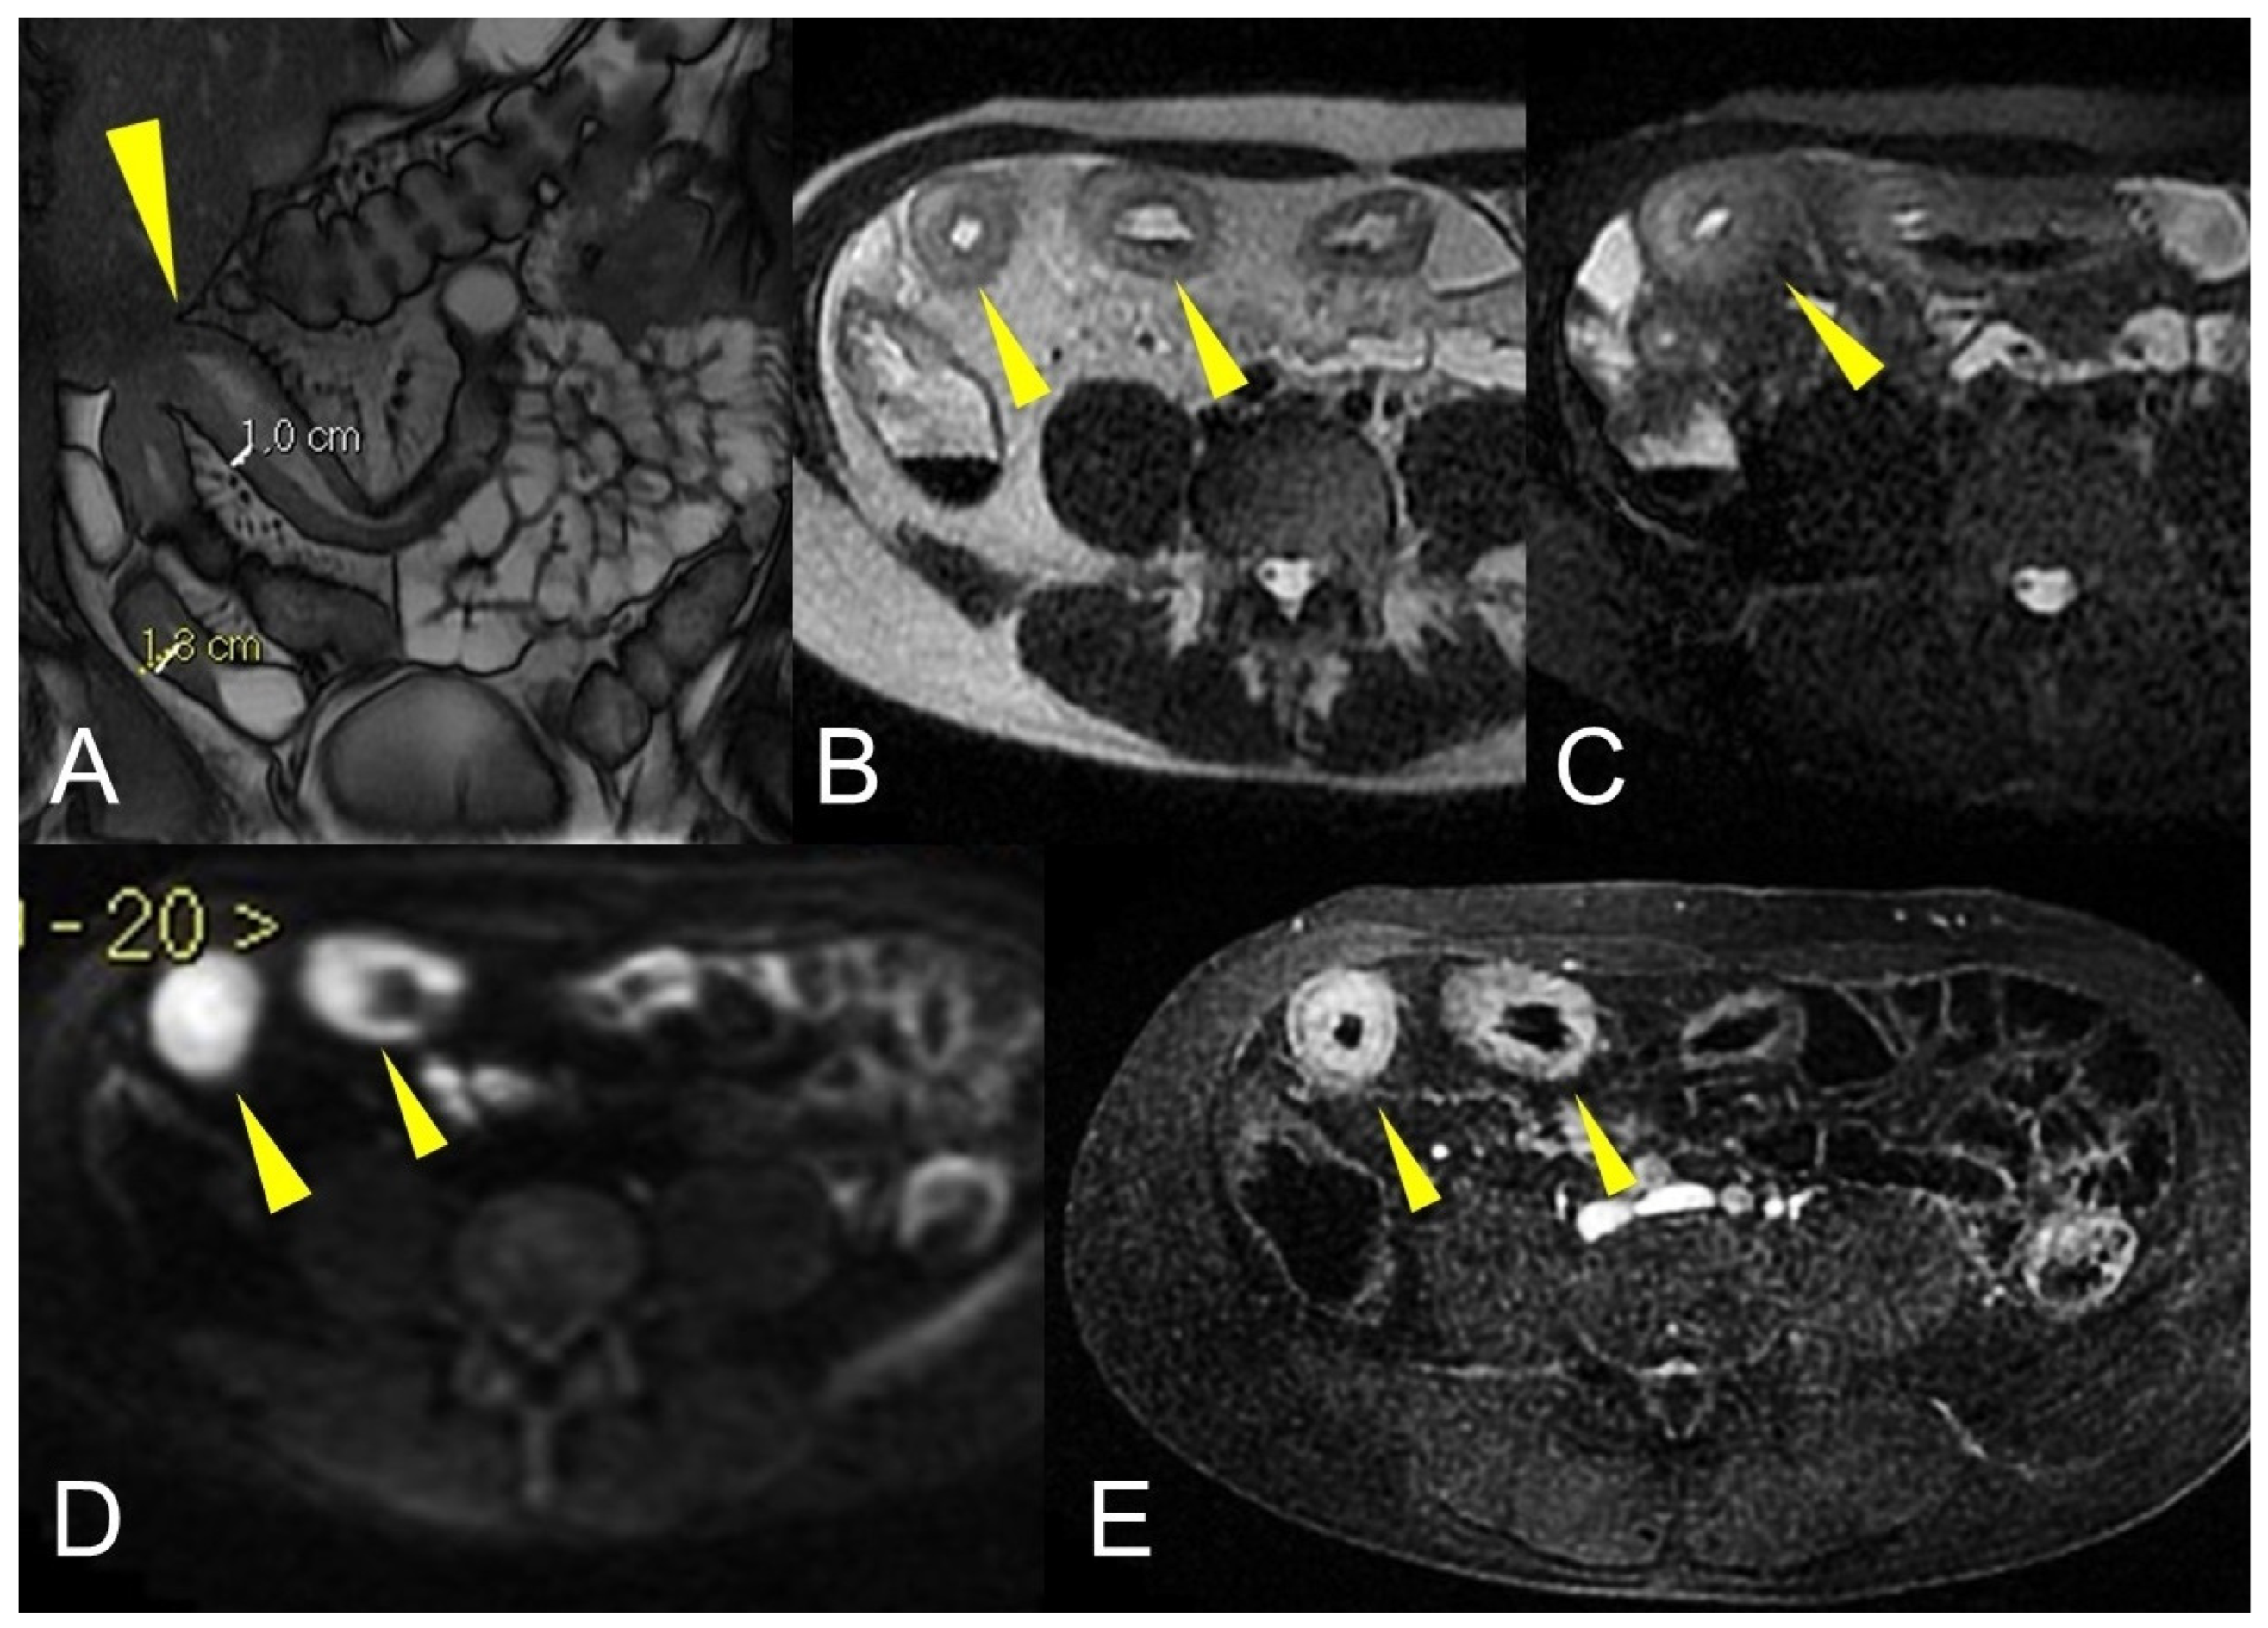

NET may present on MRI as a tiny submucosal nodule or as focal asymmetric wall thickening, with marked enhancement in the arterial phase, sometimes with hyper-vascular mesenteric enlarged lymph nodes (Figure 20). Sometimes a focal bowel wall thickening without evidence of a nodular lesion can be appreciated for the desmoplastic reaction, typical of this type of cancer. Sometimes evidence of metastases without detection of the primary tumor may occur [34,35,36,37,38,39].

Figure 20.

Example of NET in a 56-year-old female patient with abdominal pain and weight loss. (A) Axial T2-weighted, (B) DWI, and (C,D) T1-weighted after gadolinium injection images show focal asymmetric wall thickening of the distal ileum (arrow), with restriction in DWI (arrow in (B)) and marked enhancement in the arterial phase (arrow in (C,D)); an hypervascular mesenteric enlarged lymph node is also evident (arrowhead in (D)).

Other malignant disorders of the small bowel should be considered in the differential diagnosis. NET diagnosis is made when avid enhancement after gadolinium injection, desmoplastic reaction, and hyper-vascular enlarged lymph nodes are observed. NETs can become complicated with obstruction due to the desmoplastic reaction or involvement of serosa [39].